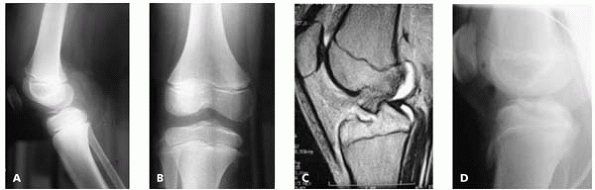

posterior cruciate ligaments in the skeletally mature results in

avulsion of the tibial spine in children. Stay out of trouble by not

missing the diagnosis on radiographs (Figs. 9-7A and B). If there is any doubt, an MRI or CT may be of assistance (Fig. 9-7C). The primary area to stay out of trouble is not to lose extension postoperatively (Fig. 9-7D). Some series have reported up to 60% of patients losing terminal extension following this injury.14

▪ FIGURE 9-7 A: Lateral radiograph demonstrating a tibial spine avulsion. B: Note the fracture is not well visualized on an AP view. C:

MRI demonstrates this fracture as well, but was probably not necessary in this case as the lateral radiograph made the diagnosis. D: Following casting in full extension, the fracture reduction was accepted as adequate. The fracture healed and the knee did not lose extension. |